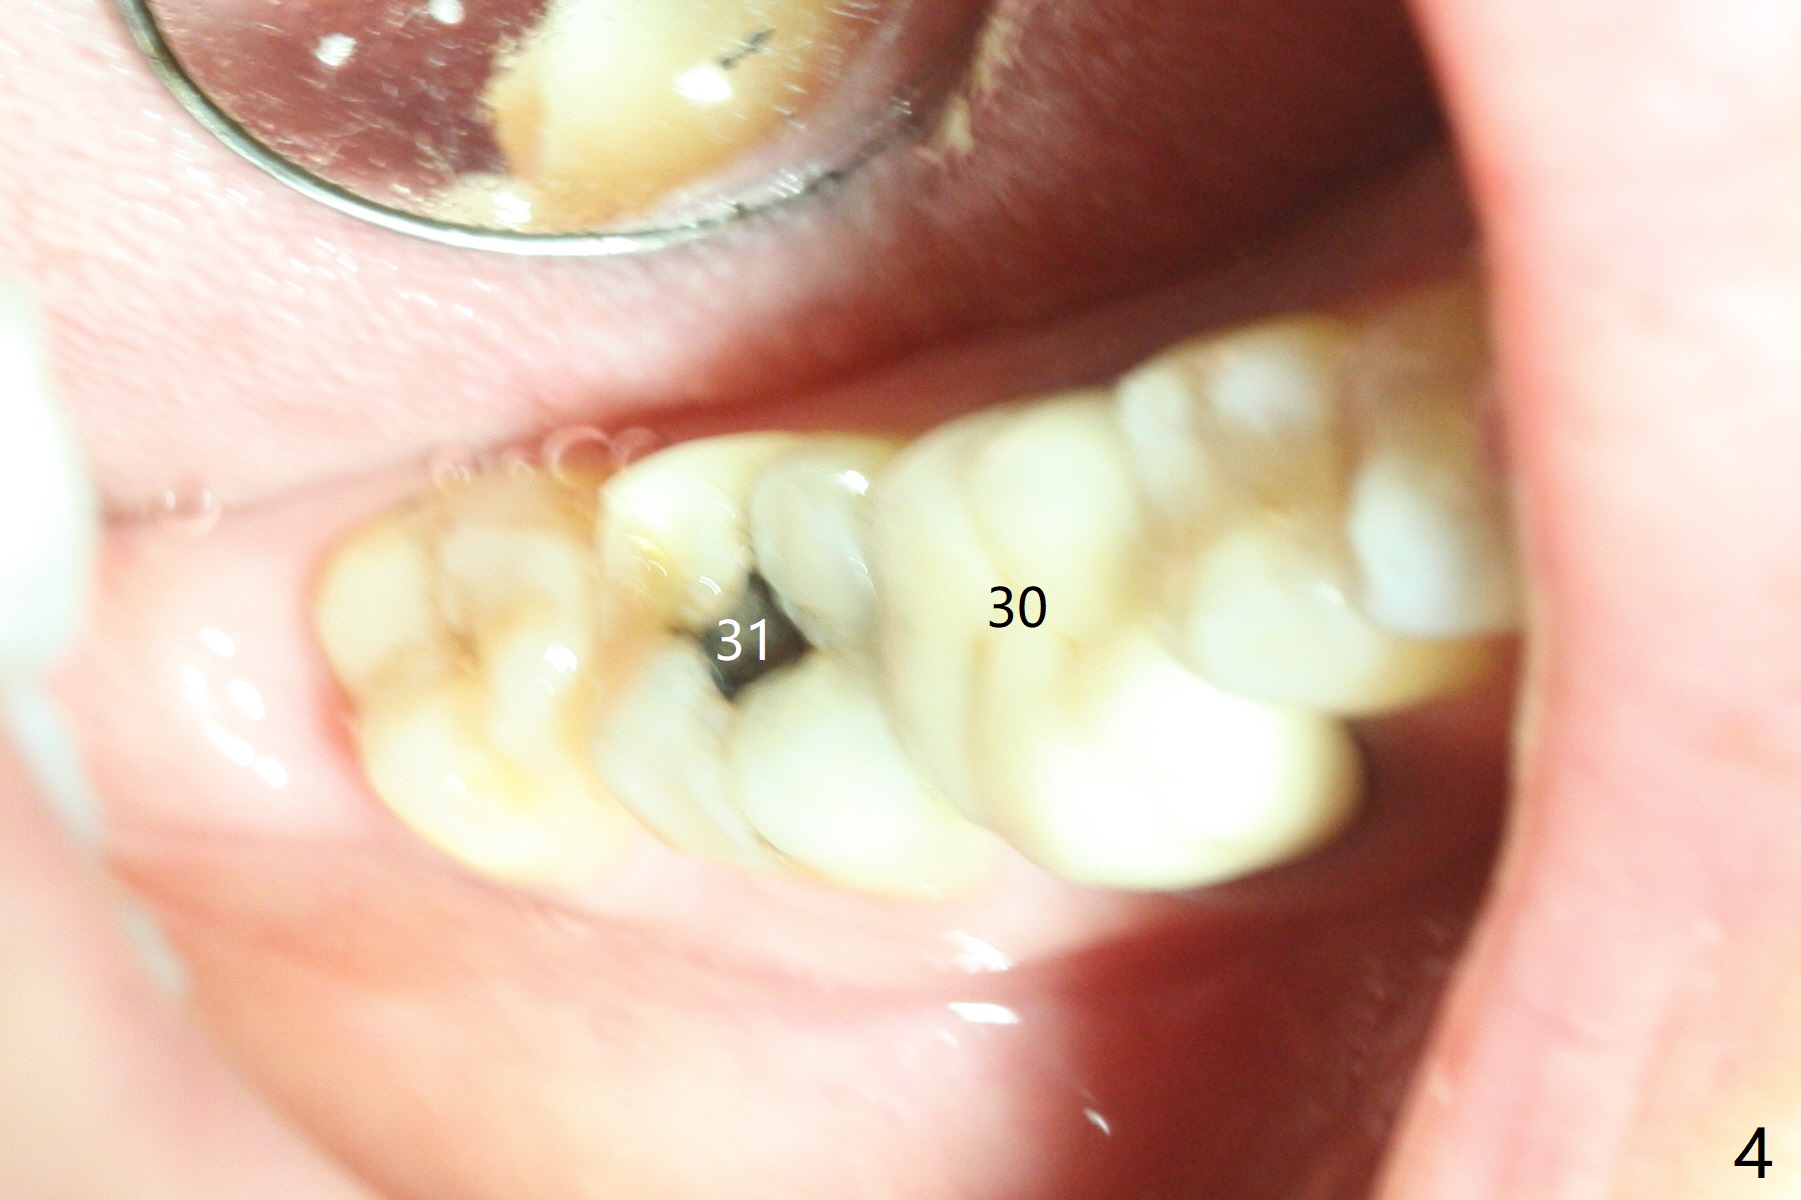

A 5x10 mm implant is intentionally placed distal at #19 using guided surgery (Fig.1). When it is osteointegrated, it will be used as an anchorage to upright the tooth #18 orthodontically. In fact the implant is mistakenly placed 1.5 mm deeper than planned without significant side effect (red dashed line: the superior border of the Inferior Alveolar Canal). The tooth #17 will be extracted before banding. The healing abutment dislodges (probably as related to deep placement of the implant) 20 days postop and is retightened. There is mild crestal bone loss 4 months postop (Fig.2). The tooth #17 is extracted with insertion of Osteogen Plug to prevent dry socket. A 5x4(2) mm cementation abutment will be placed with fabrication of a provisional with equi- or slightly subocclusal. Bands and brackets will be placed at #18-22. When open coil spring is placed between #18 and 19 with 18 ss wire, acrylic will be added to the occlusal surface of the provisional so that the tooth #18 is distalized without interference. The tooth #18 is distalized more than 1 month post placement of open coil spring (Fig.3). The tooth #18 is also lingually tilted (Fig.5), as compared to the contralateral side (Fig.4). After placement of 20 ss wire and longer coil spring, an elastic is placed between the lingual cleat of #18 and the buccal (lingual) button of #15 (Fig.5) to correct the lingual tilt. The tooth #18 is distalized ~ 1 mm shown by X-ray, although more clinically, 2.5 months post open coil spring (Fig.6). The bone density around the implant, particularly mesial, increases, as compared to Fig.2. The treatment finishes with normal overjet in the 2nd molars 11 months postop and 5 months post banding (Fig.7). It appears that the buccal groove of the lower 2nd molar (Fig.8 >) has been distalized to occlude with the mesiobuccal cusp of the upper 2nd molar (^). The width of the dense bone around the implant increases 14 months postop (3 months post cementation, Fig.9).